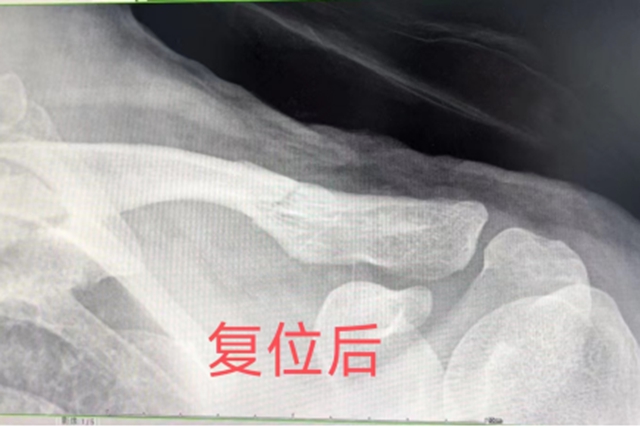

经过X光检查,小宇被确诊为锁骨骨折,且骨折移位较大。医生建议进行手术治疗,但这个消息让小宇的父母犯了难:孩子还小,正处于升学的关键时期,手术不仅会留下难看的手术瘢痕,而且二期还需要再次手术取出钢板,这对孩子的身体和心理都会造成一定的影响。

骨伤科创伤·正骨组的王念武医生接诊后,仔细查看了小宇的病情和之前的检查资料,一边耐心地听着父母讲述孩子的受伤经过和他们的担忧,一边在心里思索着治疗方案。虽然小宇的骨折移位严重,但受伤时间短,而且孩子和家属都愿意积极配合治疗,这让王医生觉得还有复位的可能。他将自己的想法向上级医师请示后,得到了支持,决定当天就为小宇进行中医手法复位。

治疗室内,王念武医生让小宇放松身体,随后便和几位医护人员默契配合开始了复位。擒拿、牵引、端提、环绕、升降…… 一系列专业而娴熟的手法在小宇的肩部施展。小宇虽然疼得直冒汗,但还是咬着牙,按照医生的指导努力配合着。时间一分一秒地过去,经过几次调整,终于,骨折部位成功复位了!大家都松了一口气,脸上露出了欣慰的笑容。随后,医生们为小宇用上了特制的杉树皮小夹板进行固定,并外敷了特色院内中药制剂。

据王念武介绍,锁骨位于皮下,俗称美人骨,位置表浅,受外力作用时易发生骨折,发生率占全身骨折的5%~10%。由于暴力导致骨折移位及肌肉牵拉,骨折后断端往往移位较大,经过手法整复及固定后绝大数可以保守治疗。